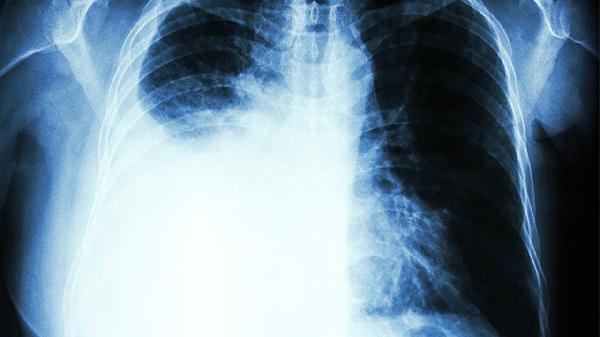

支气管软骨发育缺陷导致单向活瓣效应,气体滞留使肺叶过度膨胀。表现为进行性呼吸困难,胸片可见透亮肺叶伴纵隔移位。需急诊手术切除病变肺叶,术式包括肺叶切除术、胸腔镜下肺减容术。术后需密切监测呼吸功能。

早产儿肺泡和肺血管发育受阻,与机械通气和氧中毒相关。表现为慢性呼吸衰竭,胸片见肺野透亮度增加。治疗包括氧疗、支气管扩张剂、利尿剂。重症需家庭氧疗,预防呼吸道感染至关重要。